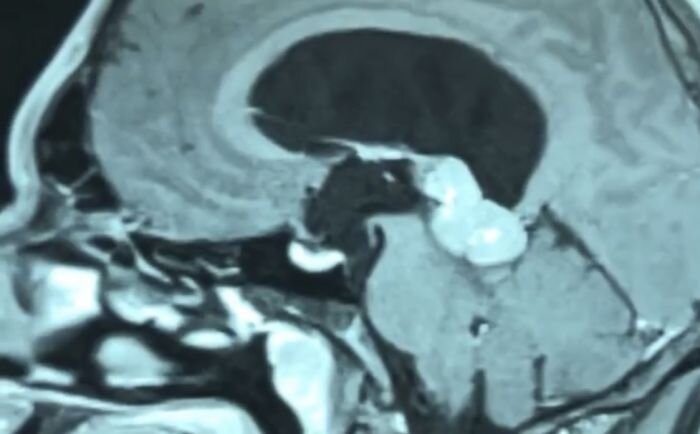

Tumors of the third ventricle of the brain

Tumors of the lateral ventricle of the brain

Epidermoid cysts of the brain

Neuroma of the bridge-cerebellar angle

Extracranial tumors of soft tissues of the head

Radiotherapy of primary tumors and secondary metastatic lesions of the brain